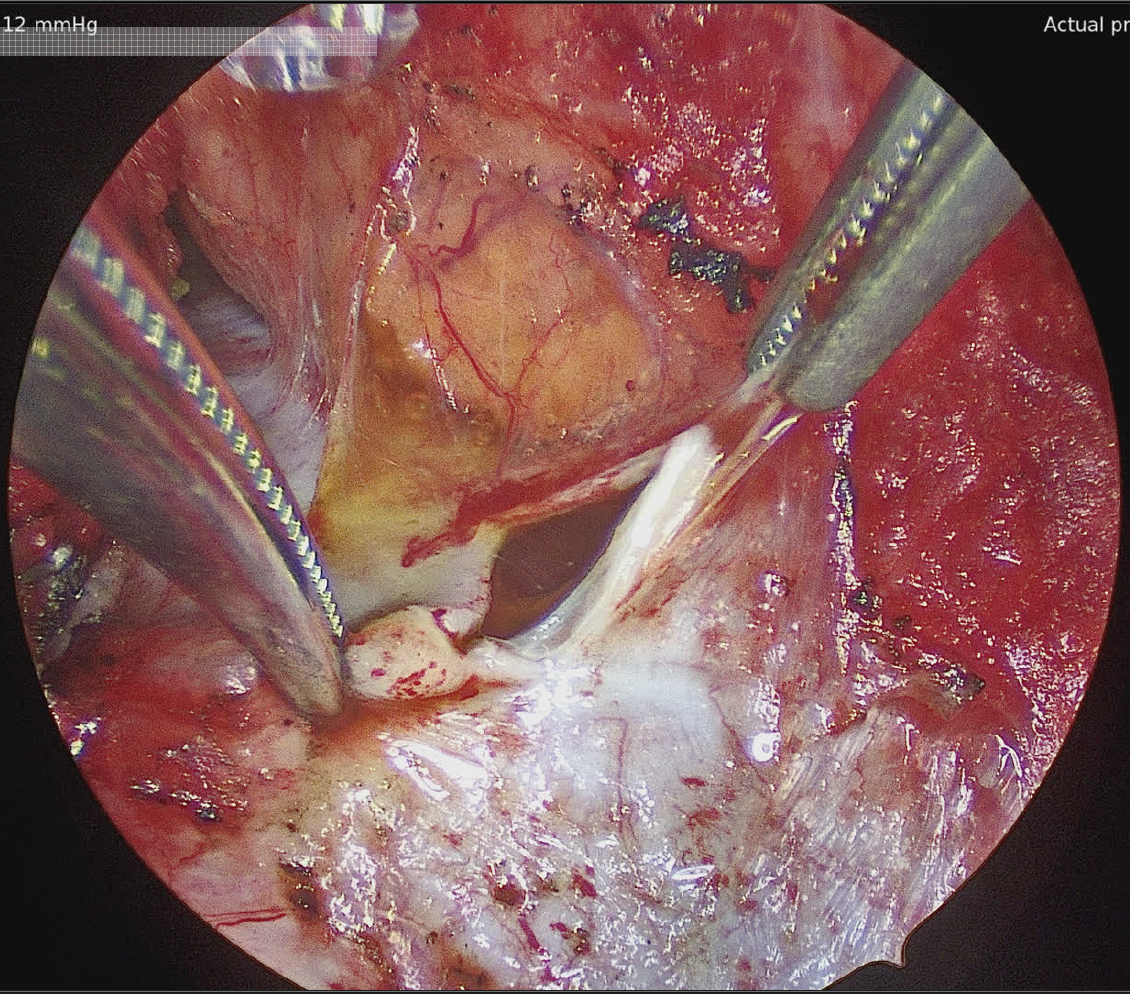

Decision-making: A transesophageal echocardiogram (TEE) was attempted due to suspected device erosion, but it was aborted due to severe cervical kyphosis. Cardiac CT revealed multi-pocketed hemopericardium, clots, thickened pericardium and aortic root edema, with the PFO closure device well-positioned. Limited sternotomy with adhesiolysis, fluid drainage, and pericardiectomy excluded erosion, confirmed an intact aorta and intracardiac device, and treated pericarditis. Fluid analysis, inconclusive for other causes, attributed the effusion to chronic pericarditis.

Discussion: Cardiac CT was pivotal in diagnosing recurrent hemorrhagic effusion and evaluating PFO device position when TEE was infeasible. It detailed effusion extent and pericardial inflammation, guiding surgical planning. Pericardiectomy confirmed device integrity, ruled out erosion—a serious complication causing bleeding or fistulas—and prevented effusion recurrence. This case highlights CT’s diagnostic precision and surgery’s role in managing chronic pericarditis and device-related risks.

Conclusion: Recurrent hemorrhagic pericardial effusion in chronic pericarditis requires evaluating diverse etiologies, including trauma, autoimmune diseases, infections, malignancy, and device complications. In patients with PFO closure devices like the Amplatzer septal occluder, excluding erosion is critical. In this case, CT-guided diagnosis and surgical intervention via sternotomy and pericardiectomy resolved the effusion, verified device position, and confirmed chronic pericarditis, emphasizing integrated imaging and surgery for managing complex effusions.